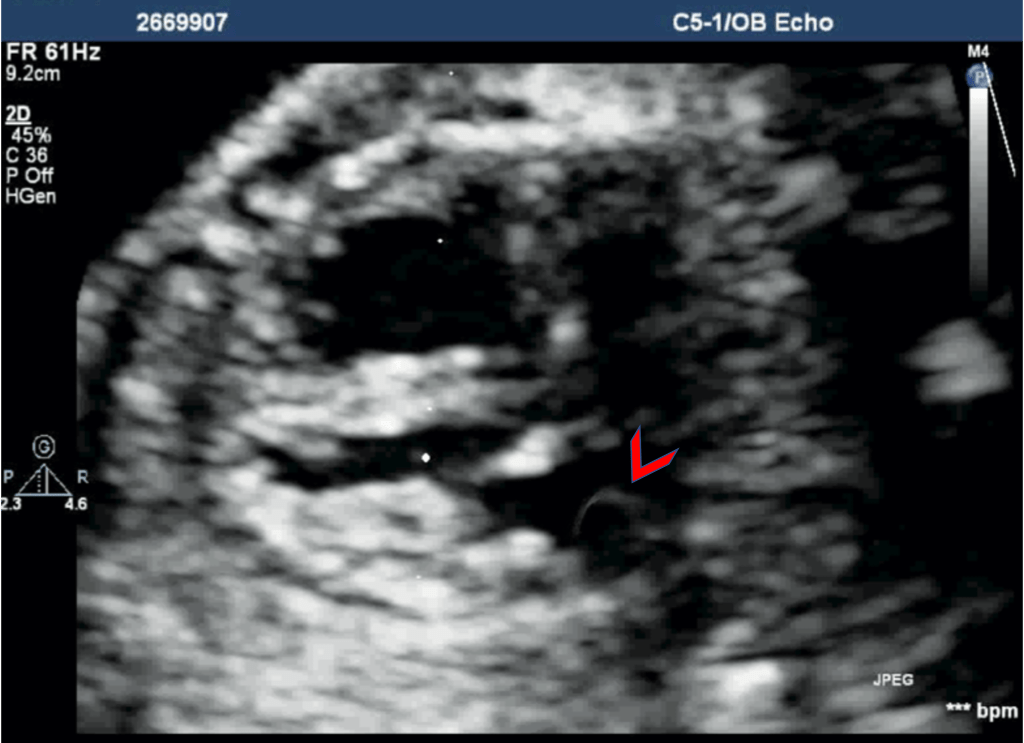

During a neonatal and pediatric echo, screening for PLSVC is part of routine echocardiography. The PLSVC can be direct demonstrated during echo and there is commonly no innominate vein with PLSVC. The drainage of PLSVC to dilated Coronary sinus is present and is well seen from the Apical 4-chamber view.

During the fetal echo, PLSVC is suspected after discovering dilated coronary sinus (CS) and a normal pulmonary venous drainage and then tracing the PLSVC cranially from dilated CS. With the introduction of the three-vessel (3VV) and the three vessels and trachea (3VT) views, PLSVC is diagnosed by the presence of a venous structure left of the pulmonary artery and arterial duct and then tracking caudally to the dilated coronary sinus.

Persistent Left SVC (PLSVC) is the most common variation of the systemic venous system. Isolated PLSVC has no clinical implications as venous blood return to the right atrium through the dilated coronary sinus. Diagnosis of PLSVC is made when a dilated coronary sinus is seen above the mitral annulus, along with the actual demonstration of LSVC. Studies have shown the coexistence of various cardiac and extra-cardiac anomalies, also an increased incidence of chromosomal anomalies with PLSVC. Association with a coarctation has been shown in meta-analysis and in a few cases, this was the only risk factor.